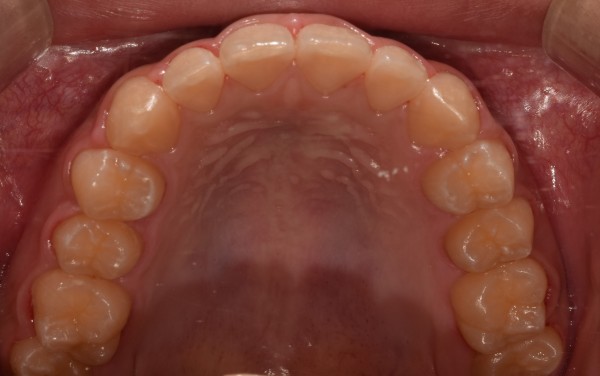

●치료명 : #15 치아 제자리로 옮기기

: #15 이소성 맹출로 교정하였던 증례입니다. 다행히 #17 맹출되기 전이라 #15 바른 위치에 옮겨 놓았습니다